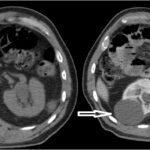

Fase sin contraste o basal

En la exploración renal se debe incluir esta frase dentro del protocolo; la fase proporciona la información inicial de una masa tumoral sospechosa, lo que permite tener un punto de referencia al compararse con las fases post-contraste. Los valores mayores a 12 UH son sospechosos de malignidad; teniendo en cuenta que el CCR es un tumor vascularizado, su atenuación aumenta a 20.

UH o más; si dichos tumores son mayores a 3 cm tienen características más heterogéneas en comparación con los tumores menores a 3 cm, que son más homogéneos.

Las calcificaciones se encuentran hasta en un 30% de los CCR y son más fácilmente visibles durante la fase basal 3-4 (Fig. 1).